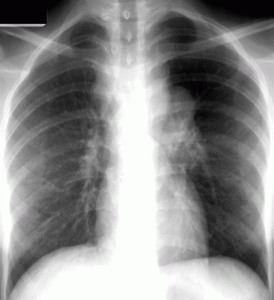

La diagnosi si basa su dati anamnestici, su segni obiettivi, su esami strumentali (radiografia, Tac, ecografia), sulla ricerca del Bacillo di Koch, a seconda del distretto interessato, nell’escreato polmonare, nel liquido pleurico, nelle urine, nelle biopsie linfonoidali. Gli esami da effettuare sono: radiografia del torace e, in casi dubbi, TAC polmonare; Tine Test con controllo della positività a 24, 48 e 72 ore; esami batteriologici, esami sierologici ( prelievo del sangue): oltre agli esami comuni (emocromo, VES, transaminasi e azotemia, la diagnosi molecolare ecc.In caso di tubercolosi localizzata in altri distretti, è indispensabile lo studio specifico dell’organo o dell’apparato colpito. La cura della tubercolosi si basa sull’utilizzo di farmaci antibiotici (la terapia antibiotica dura per un notevole periodo di tempo, dai 6 ai 12 mesi). Se la patologia è in uno stato di latenza, viene impiegato un solo farmaco antibiotico; mentre, in caso di tubercolosi attiva, una combinazione di farmaci (per evitare la resistenza agli antibiotici).